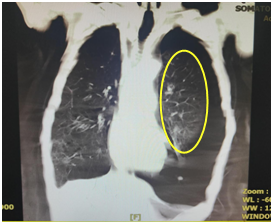

80岁的邓大爷,反复咳嗽咳痰气促10年余。近期因症状加重到我院内科住院治疗。胸部CT提示,邓大爷左侧胸腔大量气胸,两肺气肿,肺部感染。

CT检查提示左肺被压缩